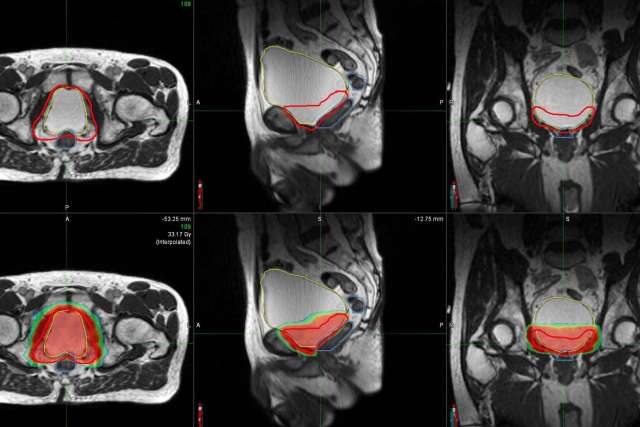

The equipment, called the MRIdian LINAC, is an improvement over older technologies, because it uses a built-in MRI to guide radiation treatment in real time, explains UCLA Health radiation oncologist Amar Kishan, MD.

“This makes a critical difference,” says Dr. Kishan. “MRIs have a much better spatial resolution than a CT scan,” which has been the traditional method to locate and map out areas that need to be treated but has limitations because it does not always provide the clearest picture of internal anatomy, particularly in the abdomen and pelvis.

Because MRIdian can see and track soft tissue and tumors in real time, it “allows physicians to adjust radiation treatment to more accurately deliver this therapy at the right dosage and to exactly the right area,” Dr. Kishan says. This form of external beam radiation therapy allows radiation oncologists to provide treatment while reducing the exposure of healthy tissues.

Because of MRIdian’s improved effectiveness in accounting for daily changes in anatomy, Dr. Kishan and his research team are able to safely deliver higher doses of radiation to patients. Dr. Kishan explains that after prostate cancer surgery, for example, the treatment is delivered in the space between the bladder and the rectum. These two organs change in size. This makes the MRI-guided treatment with better resolution an improved option for more precise prostate cancer treatment.